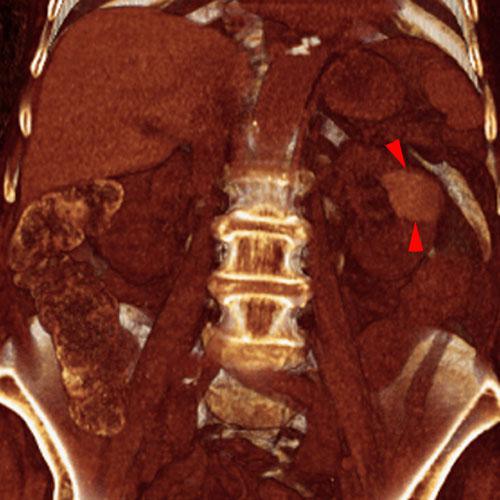

Quiste renal calcificado